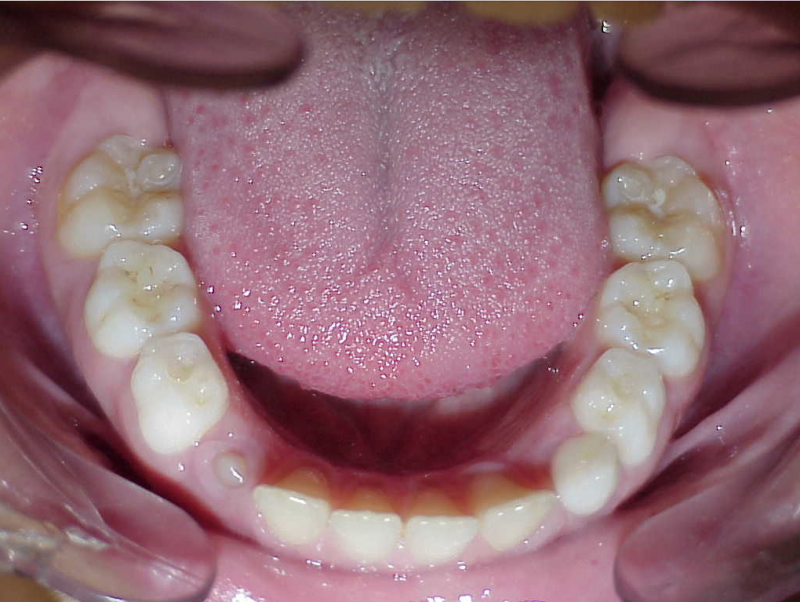

Voor behandeling

Leeftijd bij aanvang: 9 jaar

1-6 maanden Bonded Hyrax in de bovenkaak, banden/slotjes in de onderkaak met Transforce